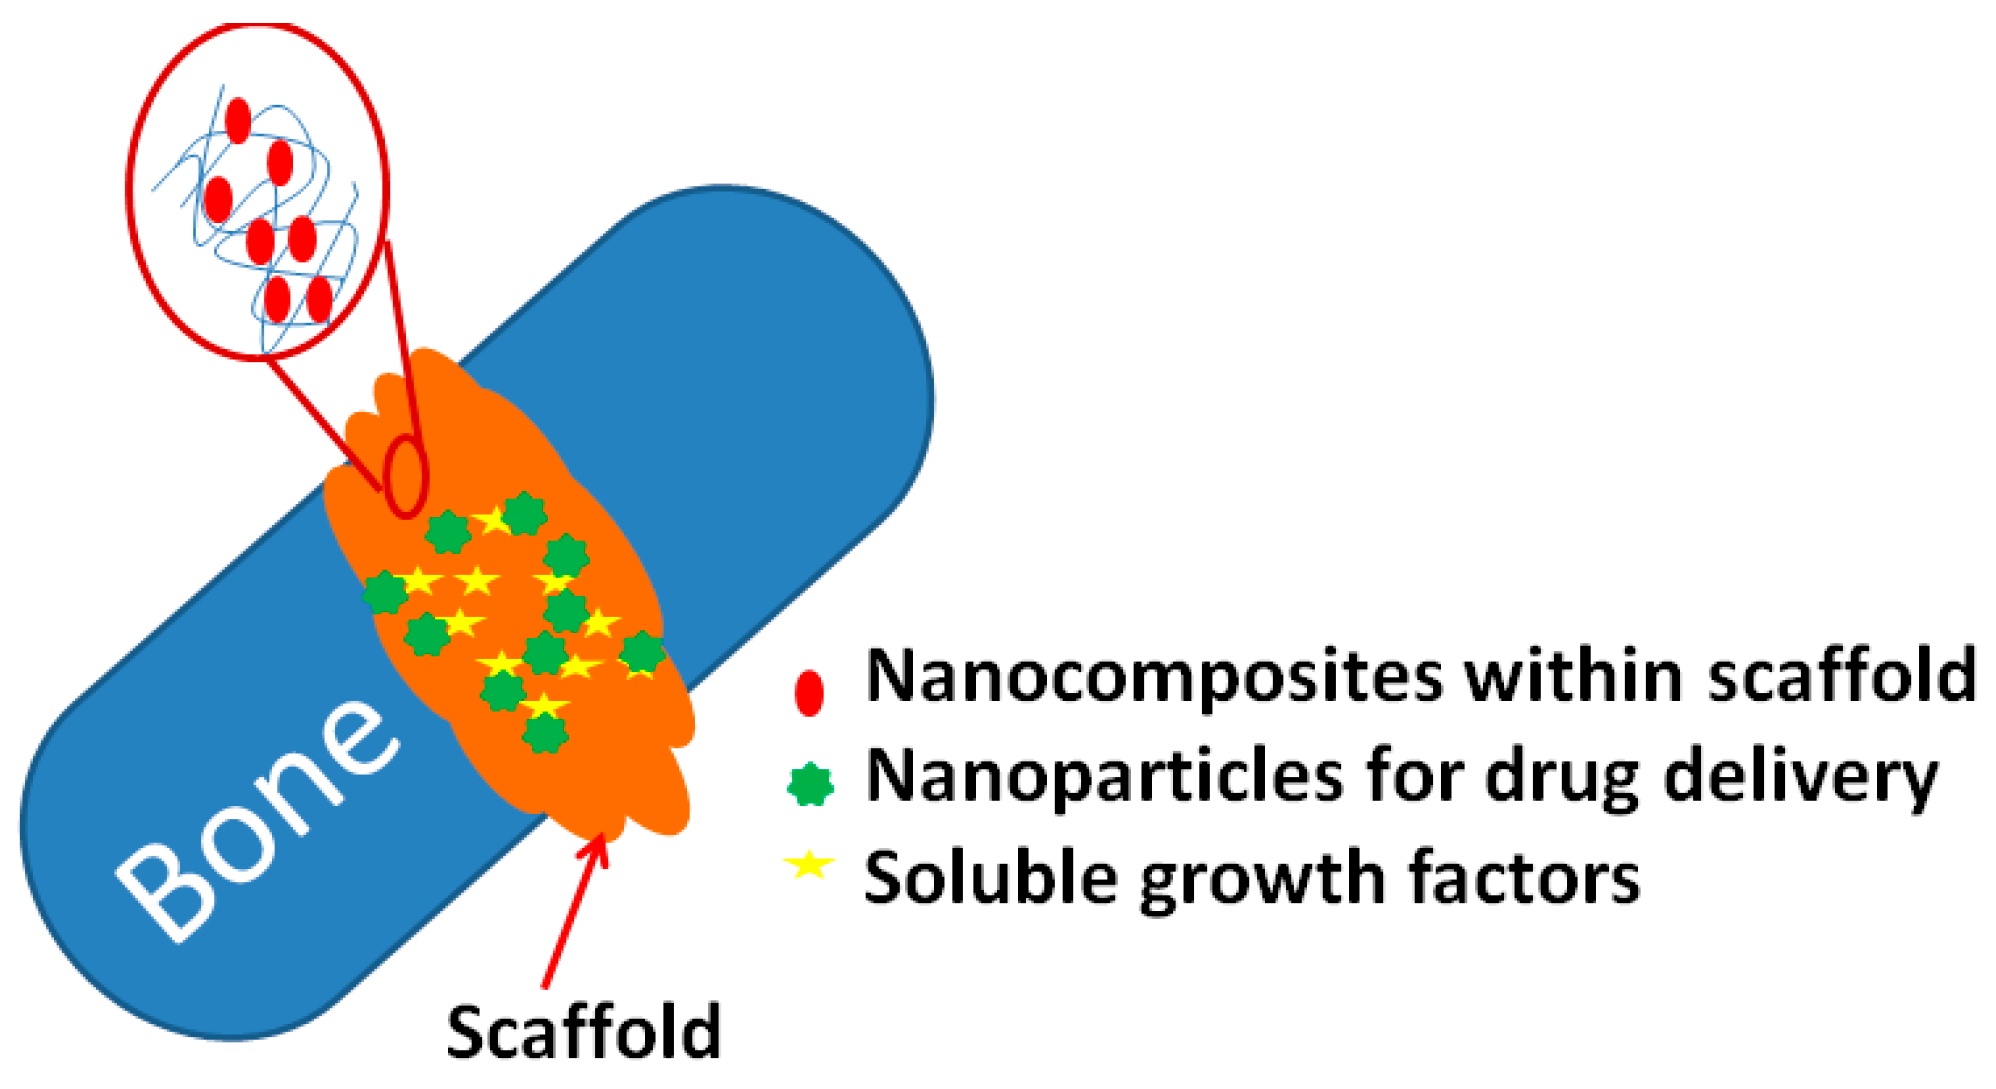

1.1. Why Nanoparticles?

3. Inorganic NPs for Hard Tissue Regeneration

3.1. Carbon Nanotubes